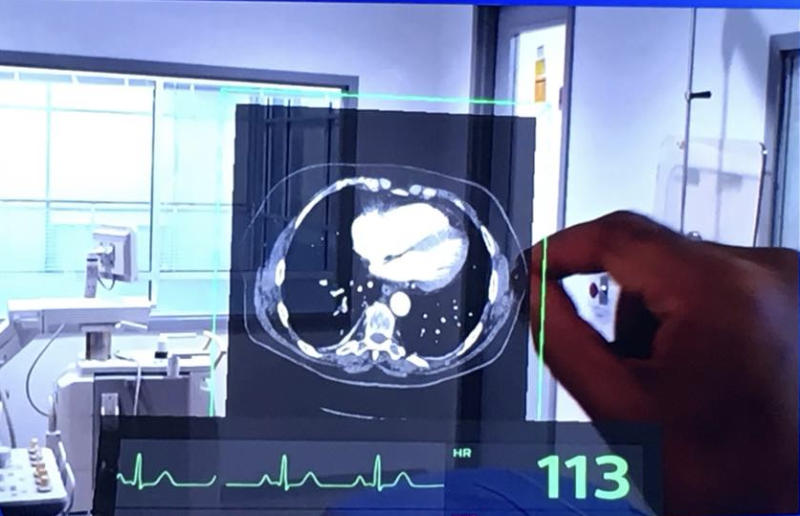

June 19, 2024 —Royal Philips, a global leader in health technology, today announced the launch of Philips Image Guided ...

Having the most efficient clinical workflows with enhanced diagnostic capabilities is a major goal for clinicians and ...

Clinicians and referring physicians need fast, secure access to both patient data and their diagnostic or viewing tool ...